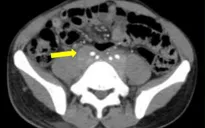

Nhu mô hạ phân thùy VII có vài khối, nốt kích thước lớn nhất 33x26mm giảm tỷ trọng trước tiêm, ngấm thuốc thì động mạch (vòng tròn đỏ), thải thuốc thì tĩnh mạch cửa (vòng tròn).